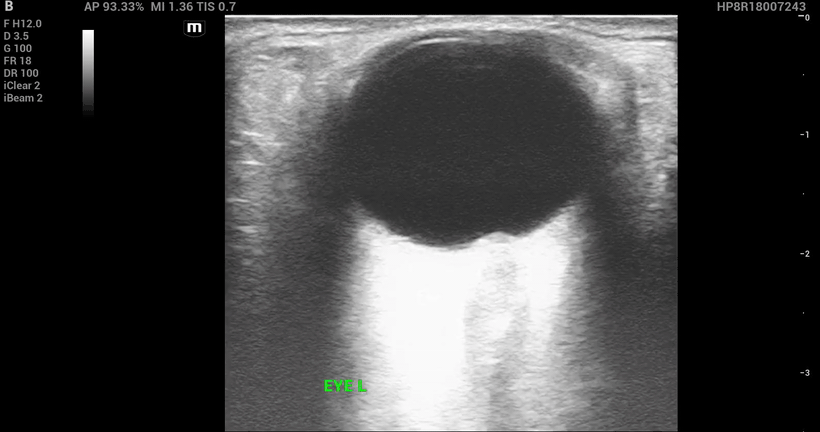

The bedside ultrasound:

Papilledema

Definition: Optic disc swelling due to increased ICP

• Normal IOP with papilledema on ultrasound